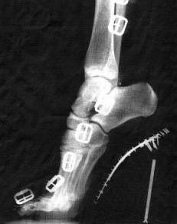

Ein Fuss in einem

High-Heel-Schuh, Röntgenfoto der deformierten

Fussstellung. Das Hauptgewicht liegt auf den

Zehenballen, und das ergibt einen schmerzhaften

Spreizfuss.

Ein Fuss in einem High-Heel-Schuh, Röntgenfoto der deformierten Fussstellung. Das Hauptgewicht liegt auf den Zehenballen, und das ergibt einen schmerzhaften Spreizfuss. [3]

Ein

Fuss in einem High-Heel-Stiefel mit Schnallen,

Röntgenfoto der deformierten Fussstellung (die

Schnallen erscheinen als

"Fensterkette"). Das Hauptgewicht

liegt auf den Zehenballen, und das provoziert

das Auseinanderdriften der Zehenballen, einen

Spreizfuss [10], und das normale Fussgewölbe

der Zehenballen wird abgeflacht [6]. Ein Fuss in einem High-Heel-Stiefel mit Schnallen, Röntgenfoto der deformierten Fussstellung (die Schnallen erscheinen als "Fensterkette") [3].

Das Hauptgewicht liegt auf den Zehenballen, und das provoziert das Auseinanderdriften der Zehenballen, einen Spreizfuss [web10], und das normale Fussgewölbe  der Zehenballen wird abgeflacht [web6]